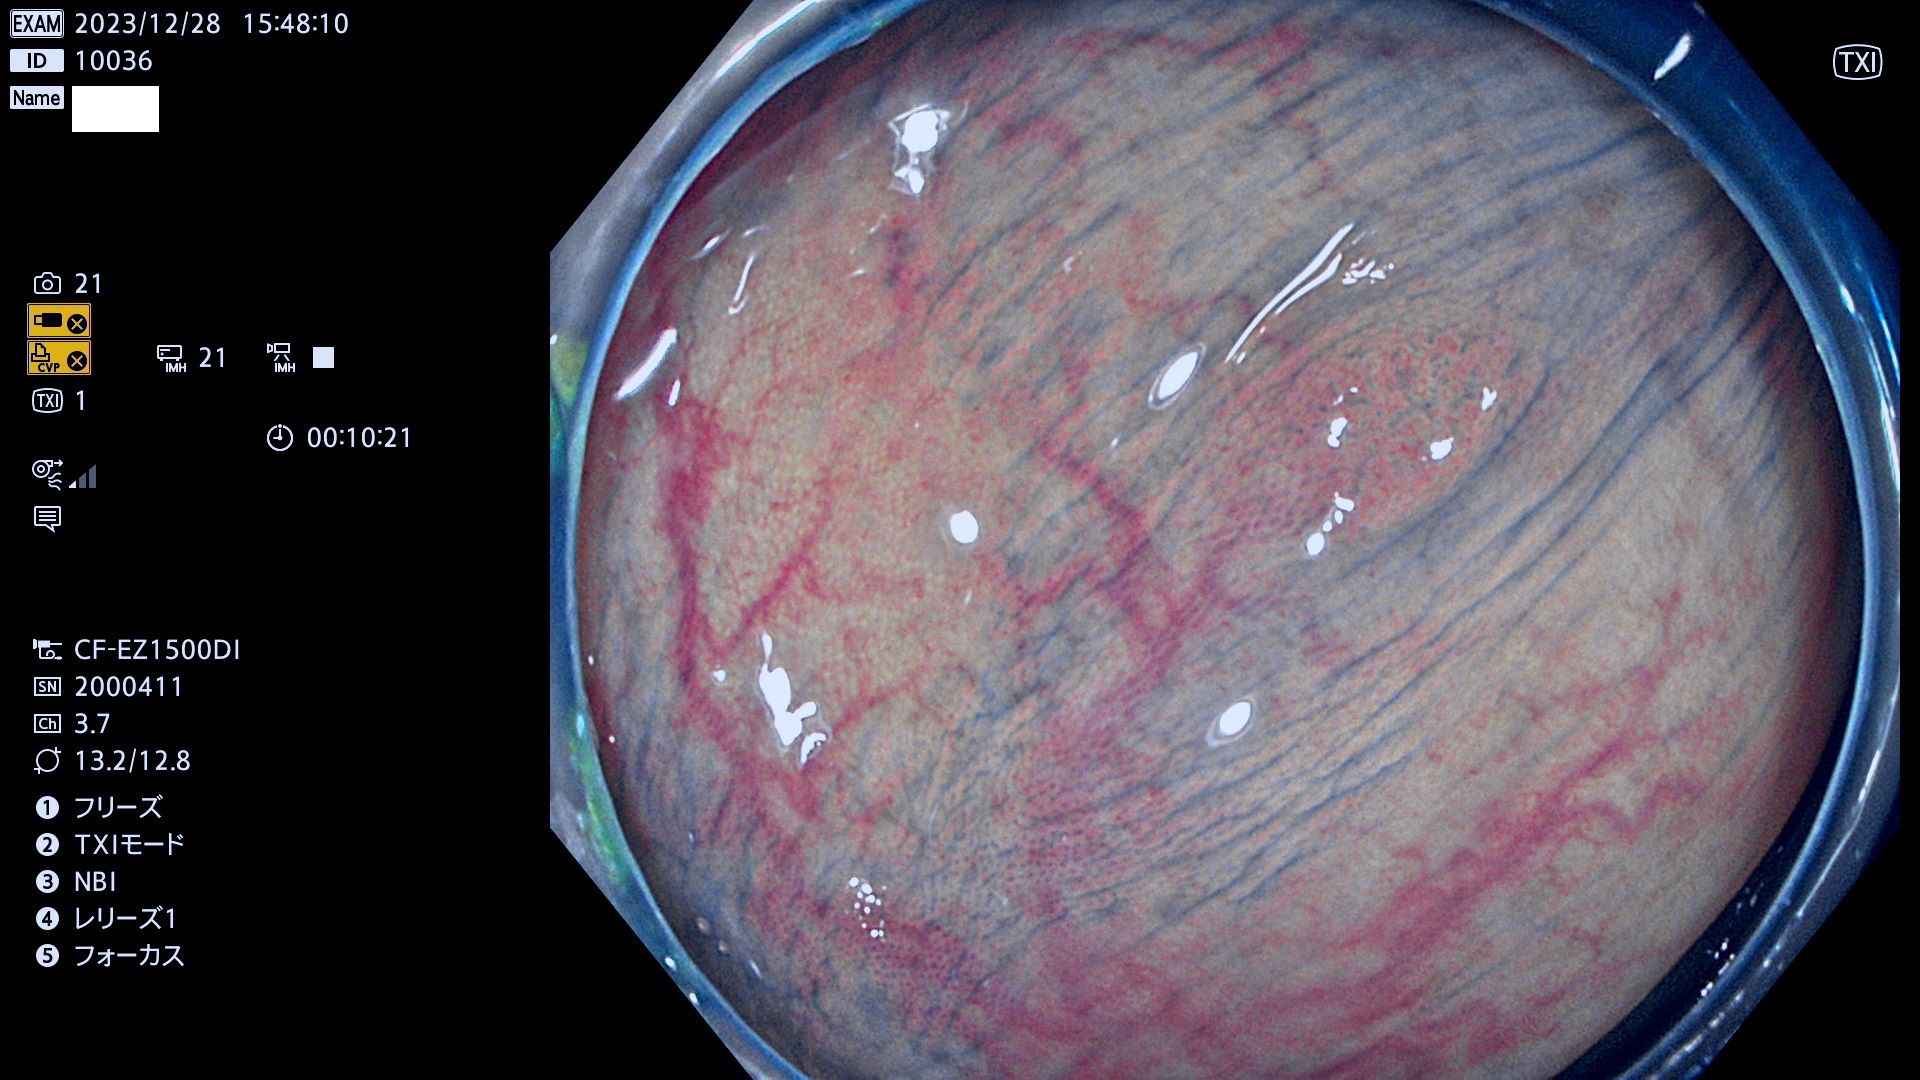

表面型腺腫(Flat Adenoma)の中で、完全に平坦な物をUb、陥凹している物をUcと呼びます。平坦隆起型(Ua)よりも、発見が難しく危険な病変です。

毎週の検査(木・金・土・日)に発見されたUb、Uc型・腺腫を、その週の日曜の夜にUPし1週間、提示します。

抽出の対象期間 2023年12月28日(木)〜12月31(日)の4日間(48件の検査)7件